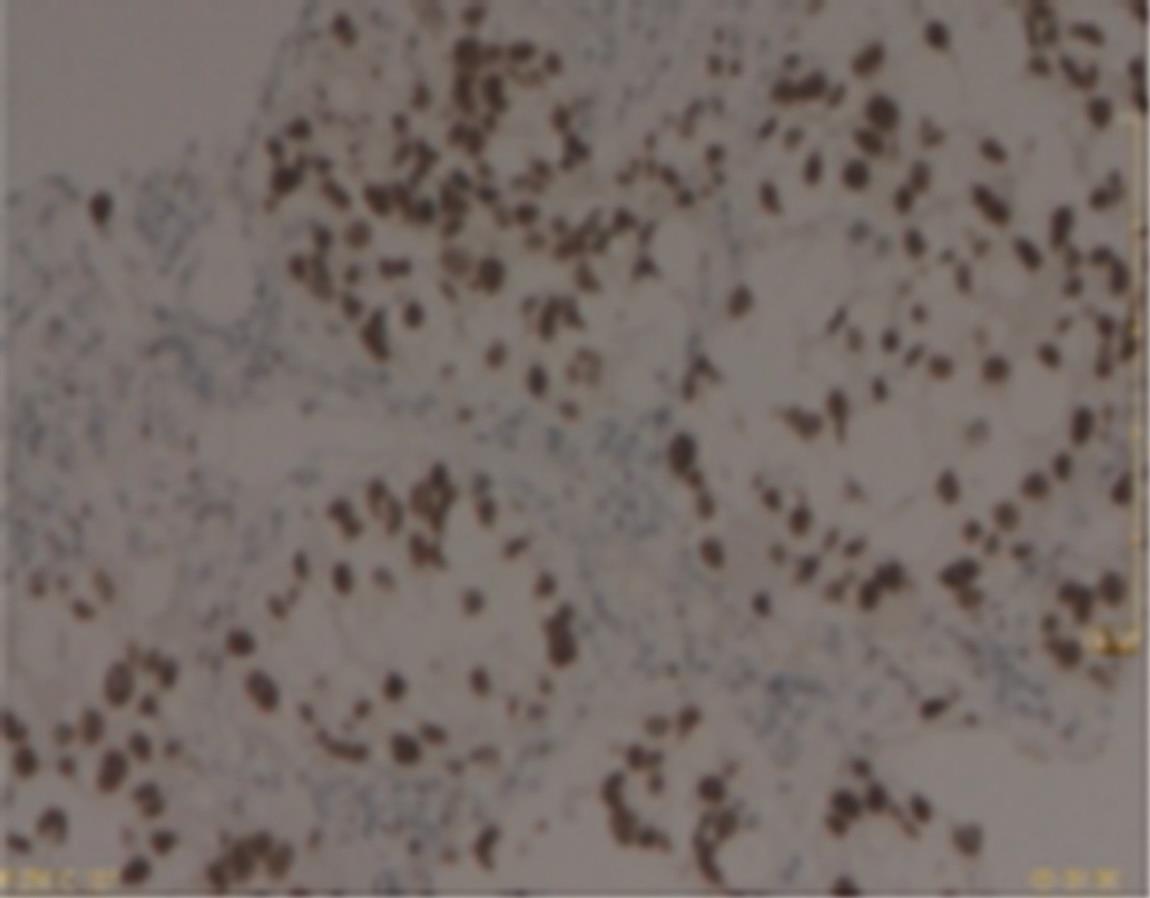

• 转移性上尿路上皮癌在维迪西妥单抗联合替雷利珠单抗新辅助治疗后行根治性肾盂癌切除术1例报道

2023, 48(8):1005-1008. DOI: 10.13406/j.cnki.cyxb.003299

摘要 (52) HTML (36) PDF 2.16 M (1929) 评论 (0) 收藏